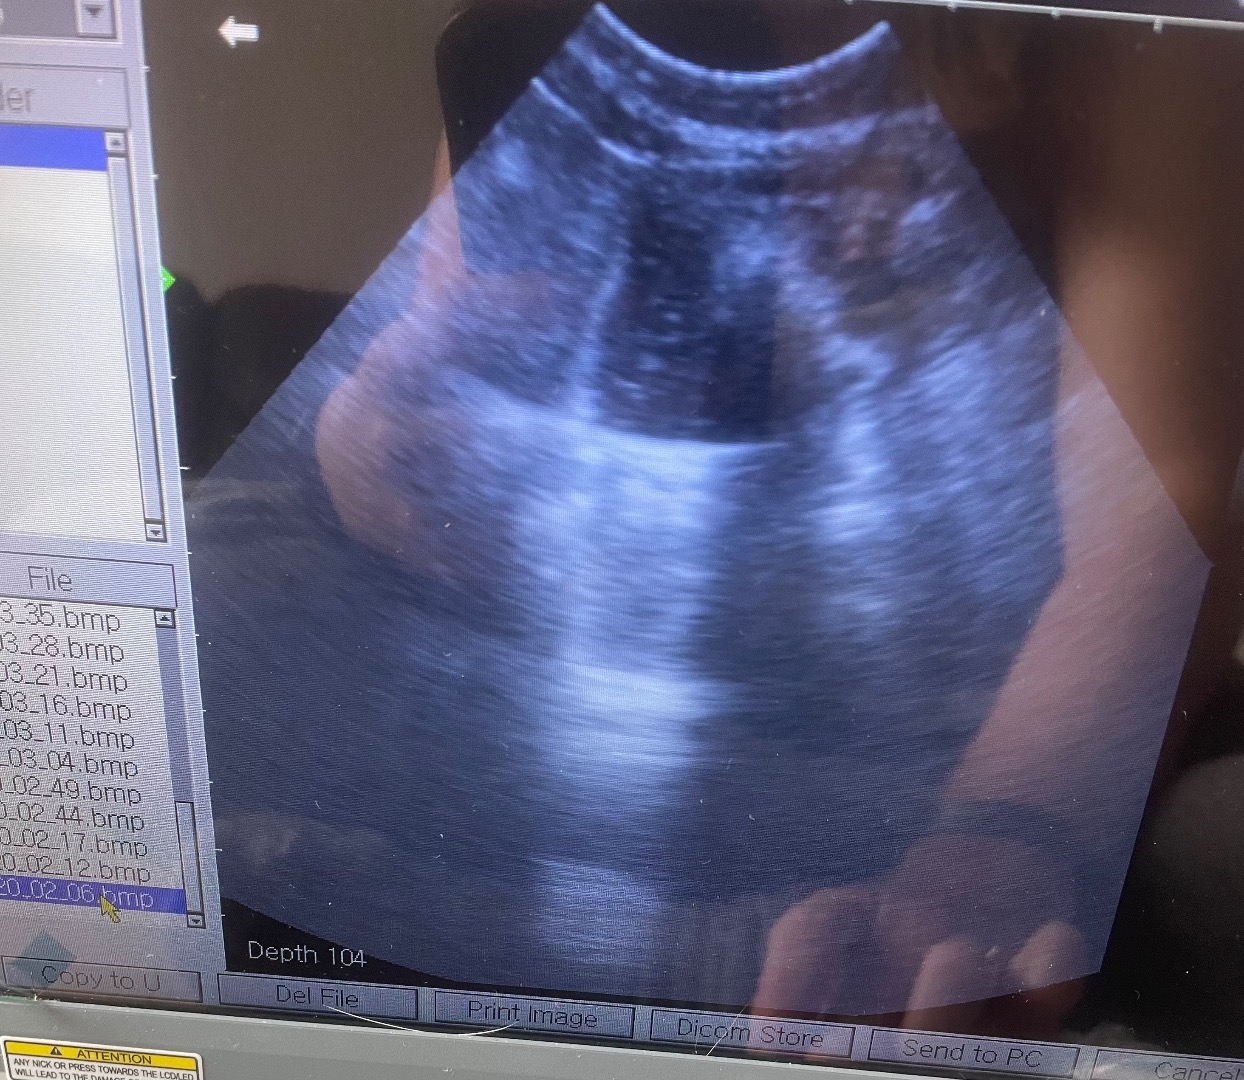

Urgent vet referral scan, no pups, lots of fluid, dog ended up have emergency operation